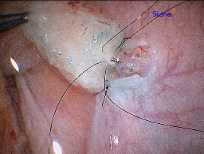

Epididymovasostomy

Epididymovasostomy is required during vasectomy reversal when there is absent sperm in the vas deferens. This signifies that a secondary epididymal obstruction has developed upstream from the vasectomy site. This situation is encountered in approximately 40% of individuals after a vasectomy. Epididymovasostomy can only be performed using a high powered operating microscope, under general anesthesia, by microsurgeons using the finest suture (10-0 nylon).